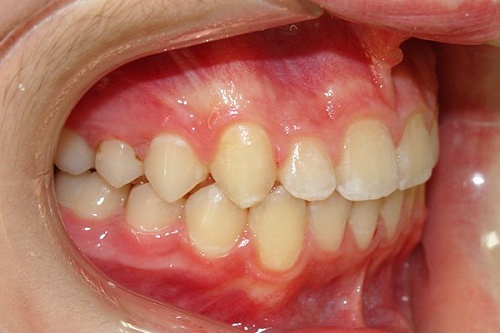

Изменения тканей, которые окружают корни зубов, к сожалению, неизбежны и с возрастом наблюдаются у всех, однако в разном объеме. Так, на развитие пародонтита влияет болезнетворная микрофлора полости рта, которая есть у каждого из нас, но на мы в силах повлиять на ее количество.

Сохранить зубы и пародонт помогает правильная гигиена полости рта дома и в кресле стоматолога, а также своевременное протезирование и имплантация, которые замещают удаленные зубы и равномерно распределяют жевательную нагрузку, не позволяя костной ткани атрофироваться.

Таким образом, по мнению стоматологов, риск возникновения болезней десен на 80% зависит от сознательности самого пациента.